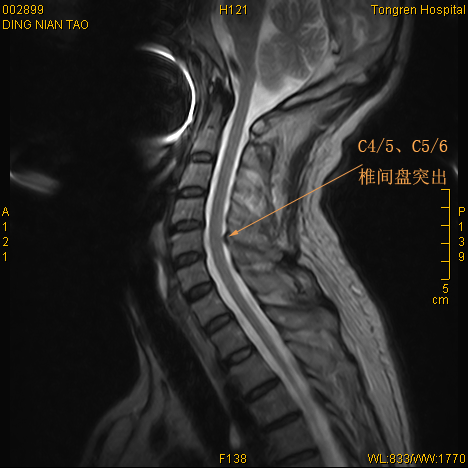

颈椎间盘突出欲北上求医,后花1000元于东台同仁医院治愈